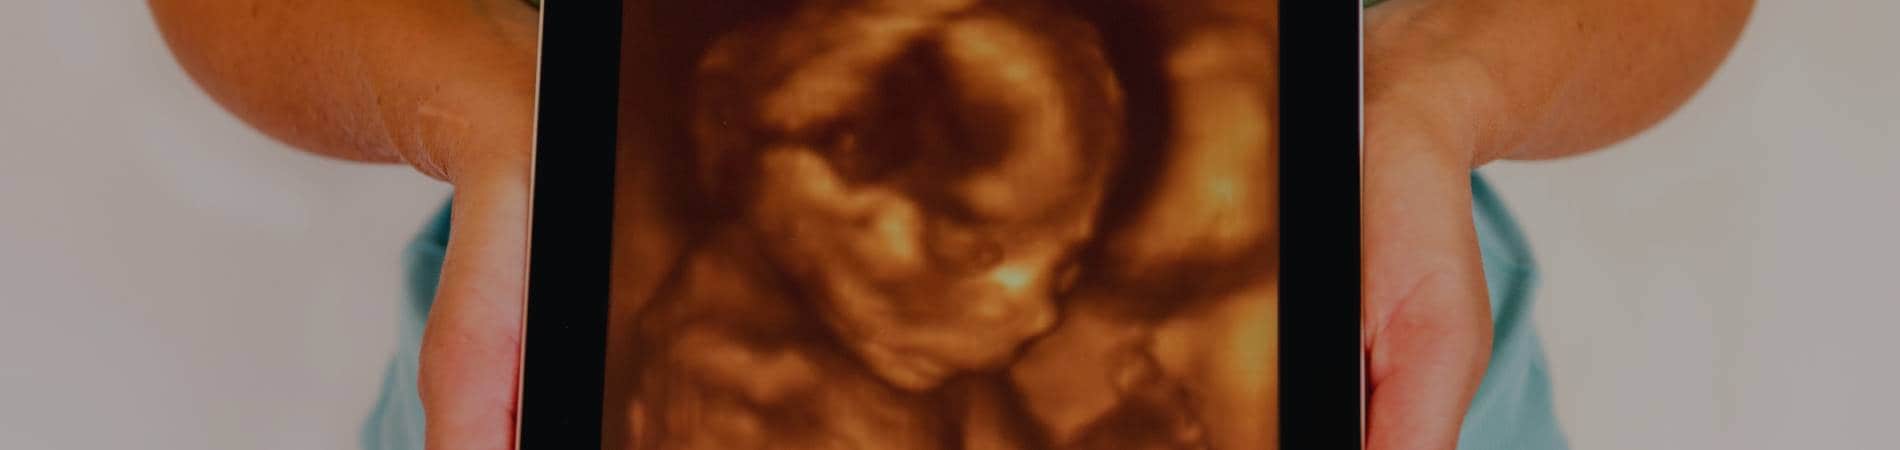

Our 3D ultrasound service allows us to take black-and-white pictures of your unborn child while in the mother's womb in terrific detail. You will be able to see the baby's features and position and a glimpse into a day in the life inside the mom's womb. This a wonderful chance for mom and dad to get acquainted with their child in our office or at your own home. Many parents opt to find out if the baby is a boy or a girl during 3D sonograms so they know whether to start decorating the room in pink or blue. Contact us today for professional ultrasound services in clear 3D imagery!